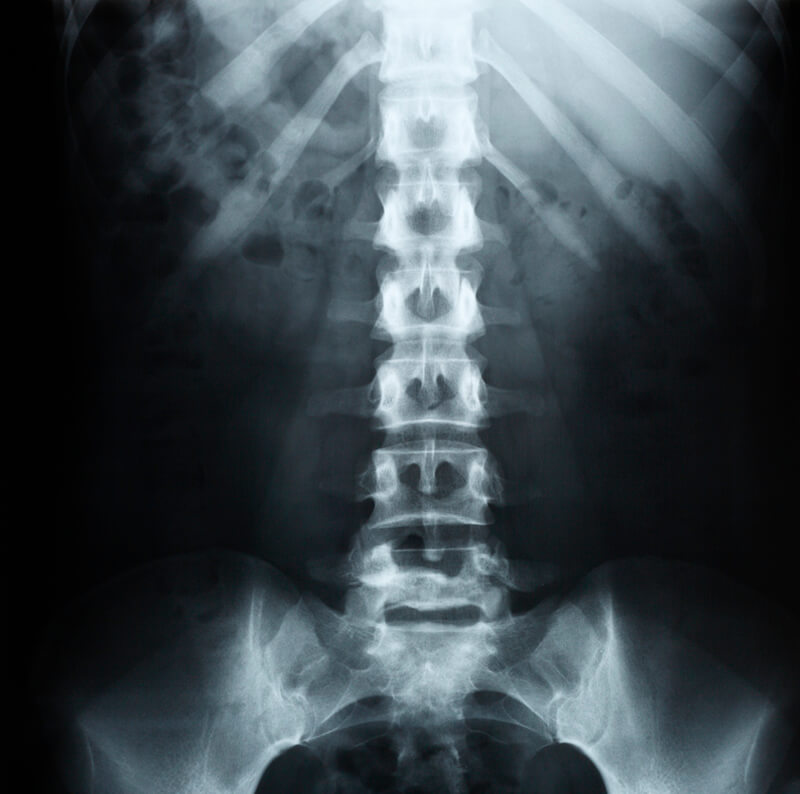

Rx colonna lombare in due proiezioni, come si esegue?

L’esame rx colonna lombosacrale in due proiezioni prevede due proiezioni di base, una antero-posteriore e una latero-laterale, alle quali si possono aggiungere delle proiezioni accessorie (proiezioni oblique) se ci sono dubbi diagnostici o se espressamente indicato sulla prescrizione; durante l’indagine il paziente può essere posizionato in ortostatismo (sotto carico) o disteso, dovrà appoggiare l’area interessata in corrispondenza del rilevatore di immagini (in stazione eretta o supino) e gli potrà esser chiesto di mantenere l’apnea per alcuni secondi per ottenere immagini più precise.